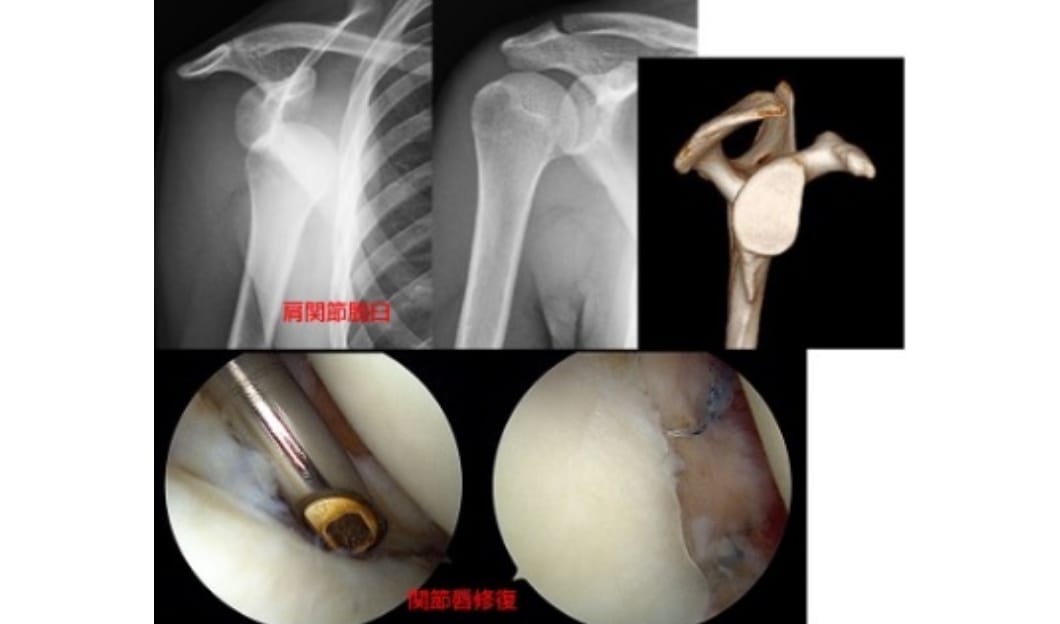

反復性肩関節脱臼

脱臼を繰り返し、スポーツや日常生活に支障が出る状態です。状態にあわせまずは鏡視下バンカート修復手術を検討します。